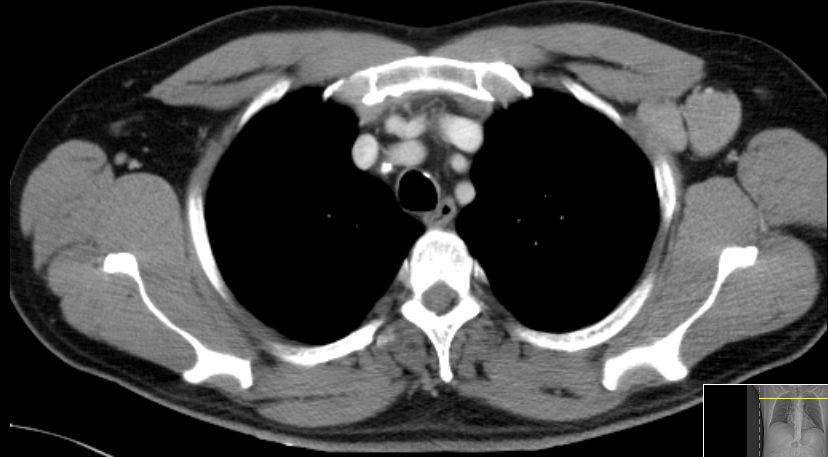

| thorakal | 21-jährige Frau mit Morbus Hodgkin mediastinal und zervikal beiderseits. Stadium IIA, Risikofaktor: hohe BSG. Noduläre Sklerose. | ||